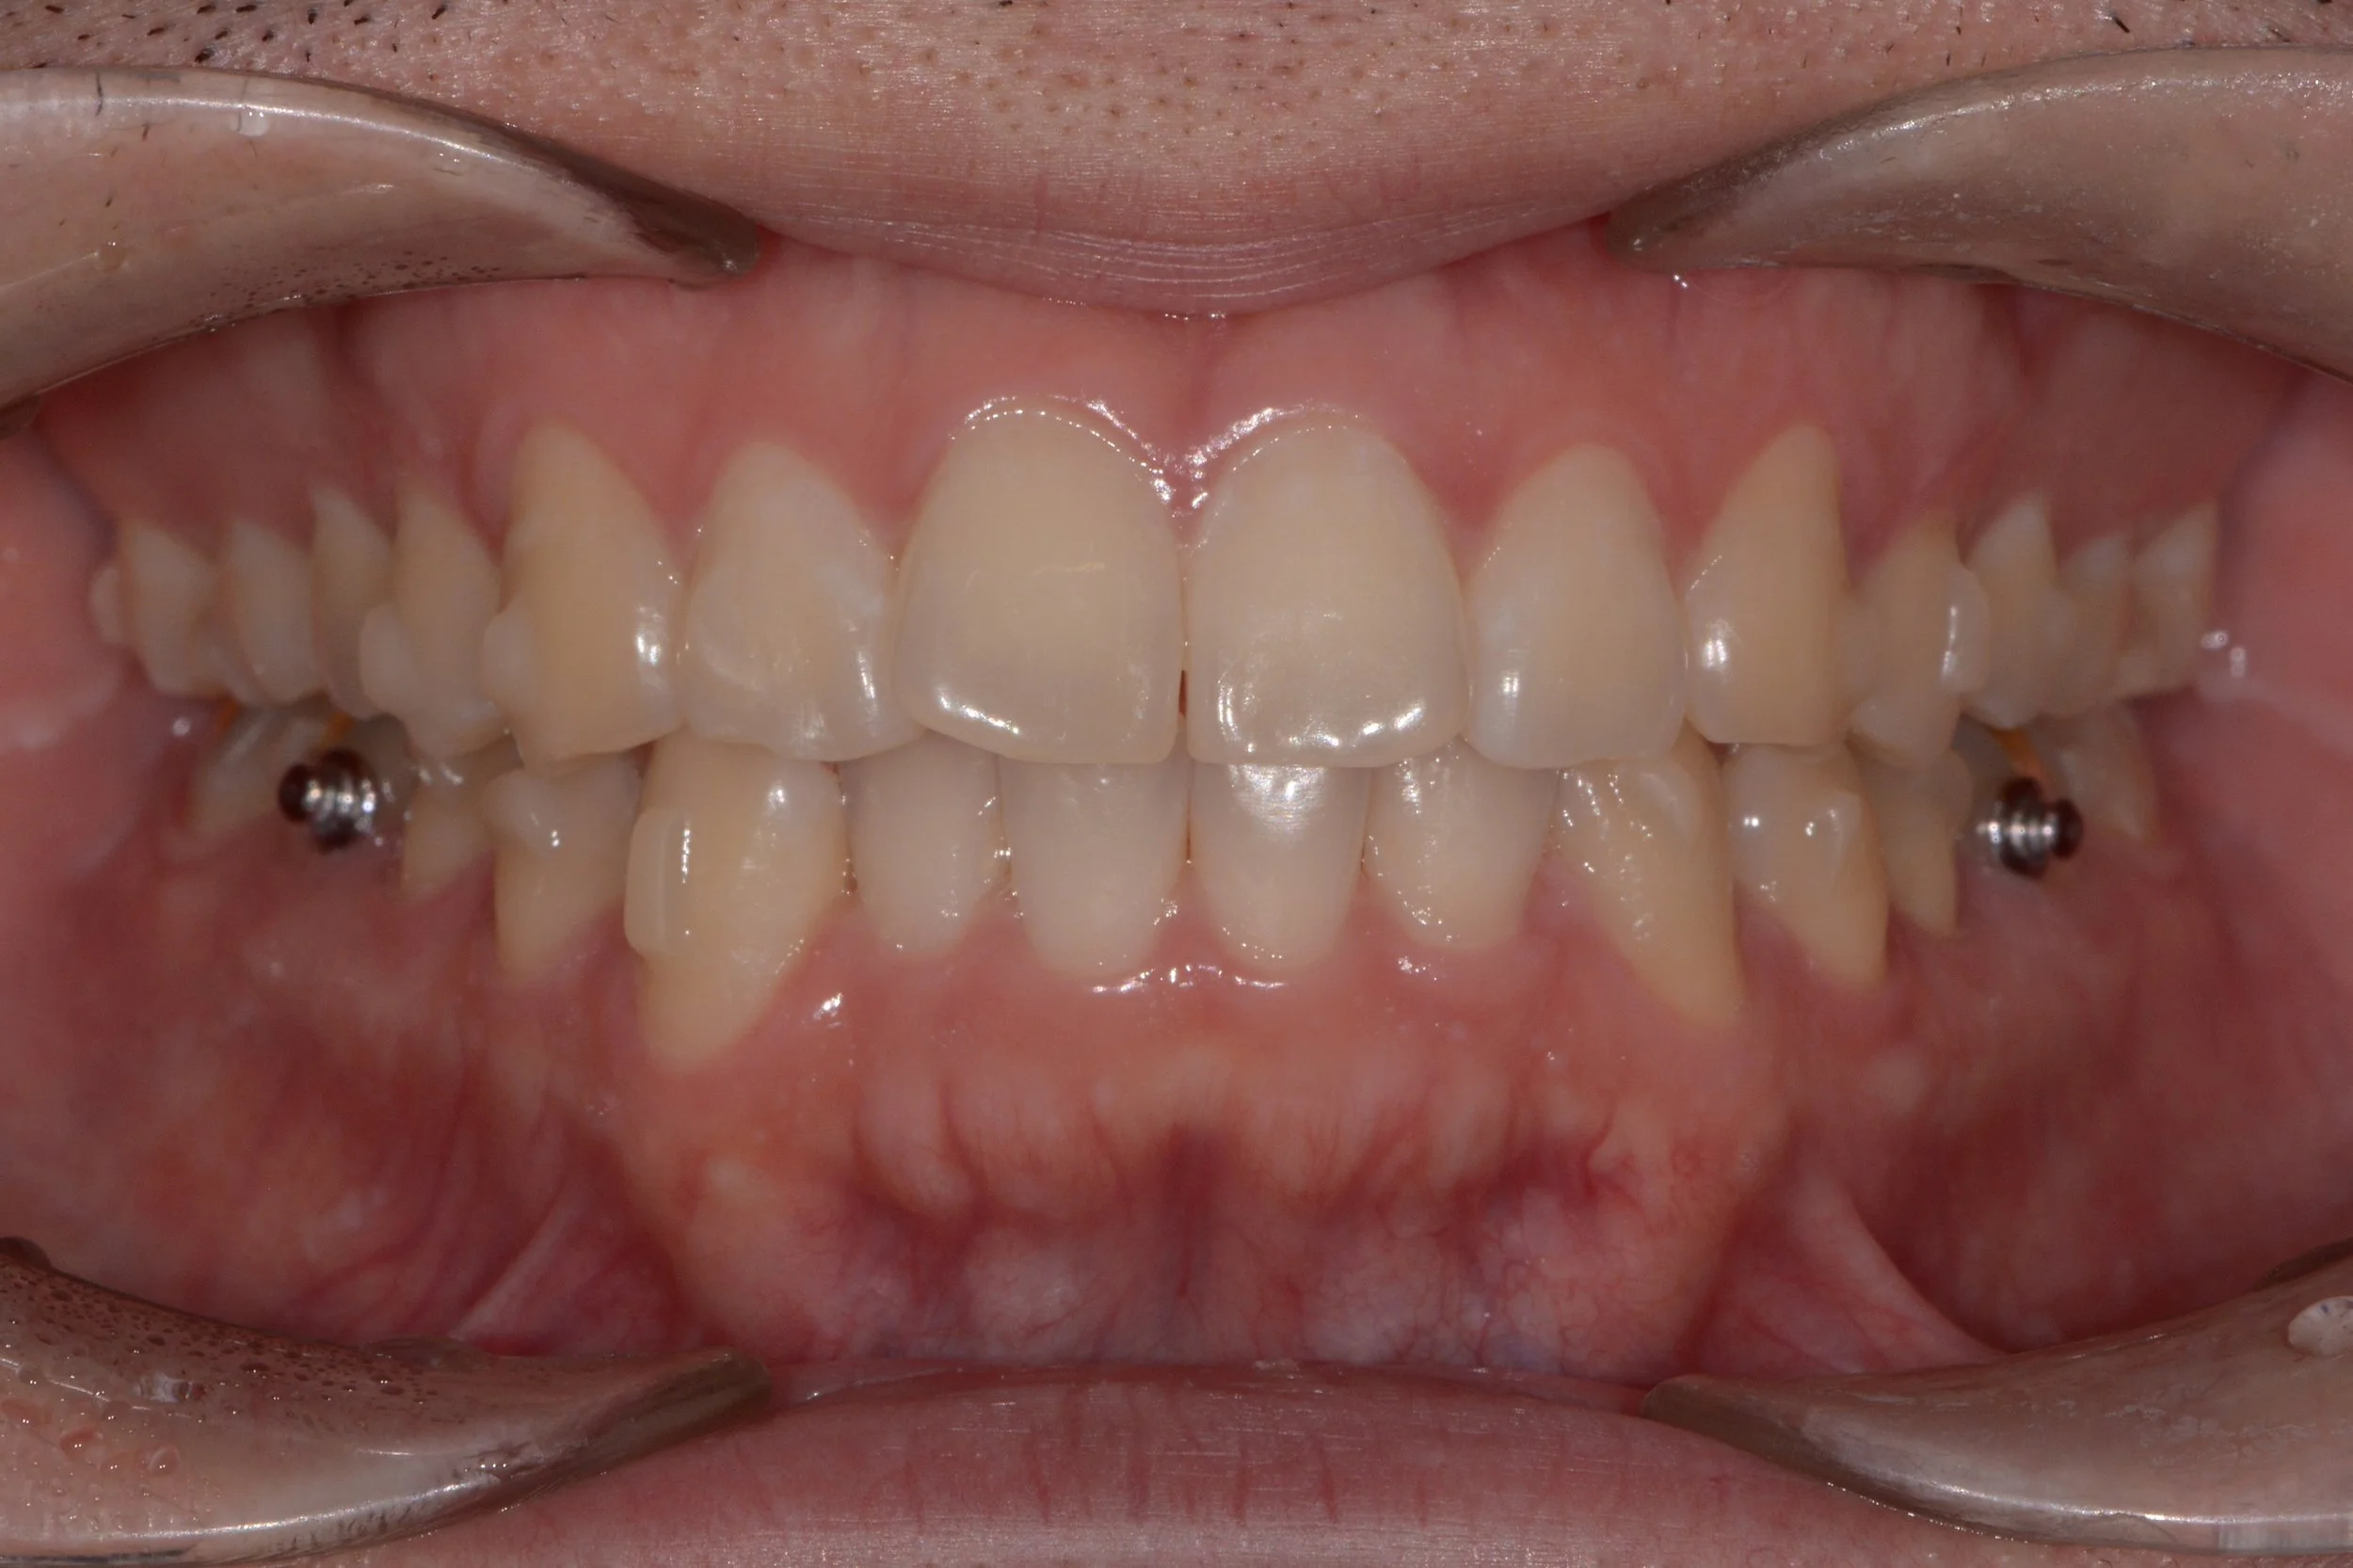

투명교정 치료 전